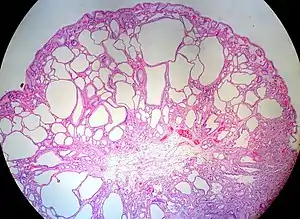

| Juvenile Polyp | Upper GI tract and colon | Cystically dilated glands with expanded lamina propria | Not inherently, may develop dysplasia | ![]() |

Juvenile polyposis syndrome, identical polyps in Cronkhite–Canada syndrome |